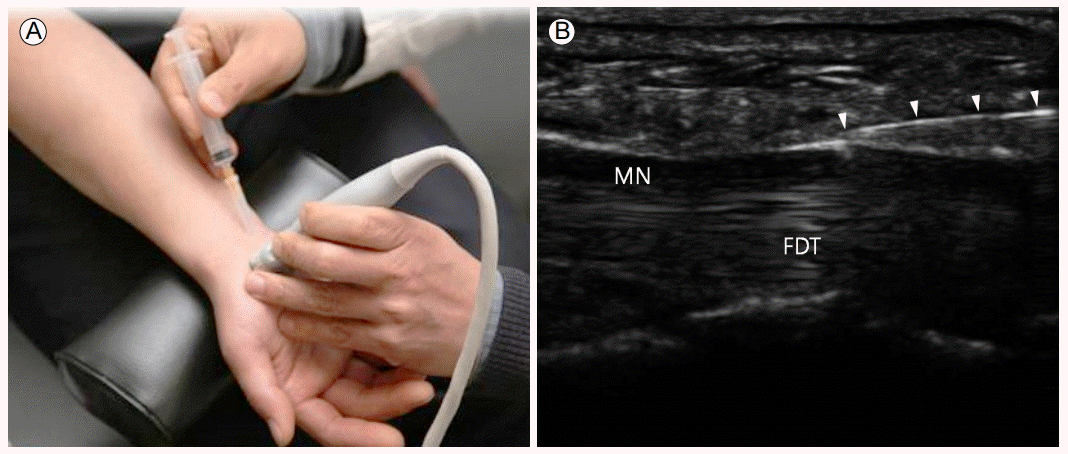

●주사치료 : 초음파를 통해 위치를 확인하고 스테로이드제 약물을 주사합니다.